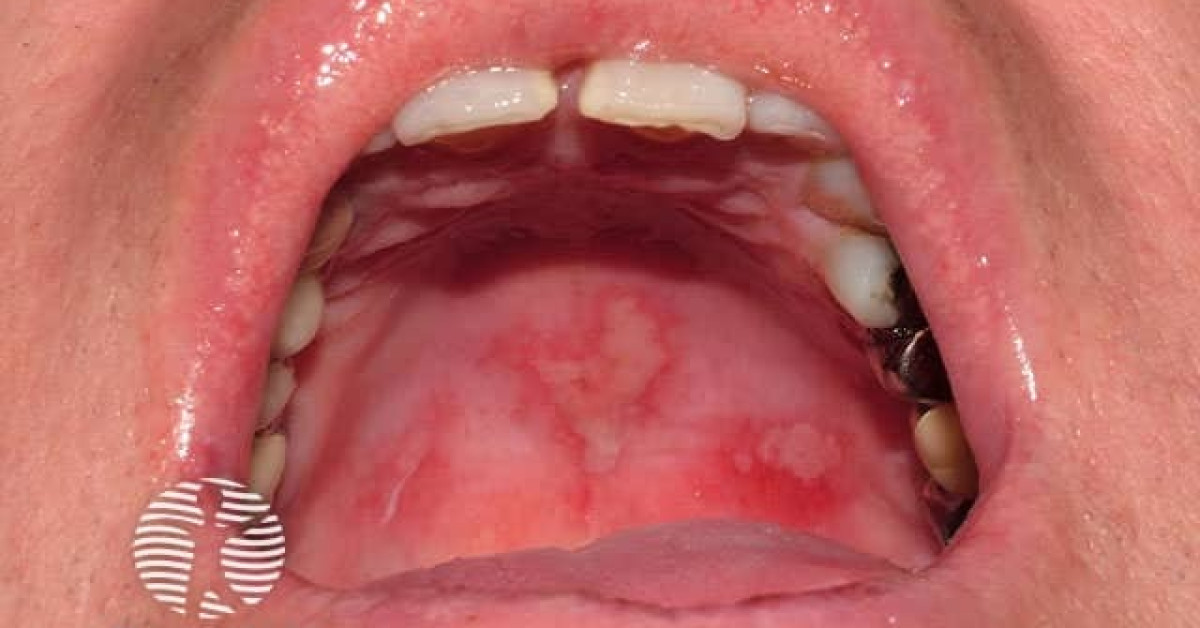

Fixed drug eruption (fde) refers to solitary or multiple oval plaques that arise over a few hours and may have central blisters. Fixed drug eruption (fde) is a distinctive type of cutaneous drug reaction that characteristically recurs in the same locations. The term fixed drug eruption (fde) describes the development of one or more annular or oval erythematous patches as a result of. Fixed drug eruptions (fdes) are dermatological manifestations of drug reactions that often occur in the same location upon re.

67yearold African American male who developed two asymptomatic